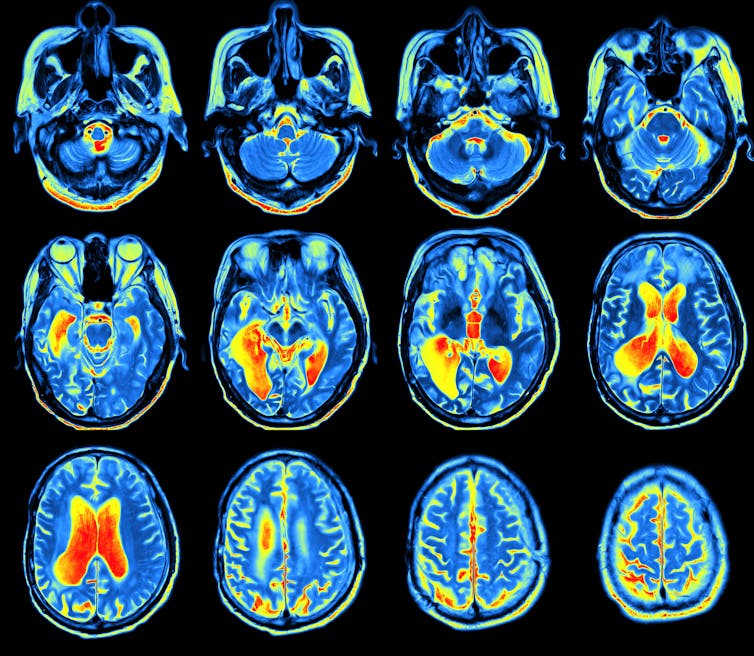

Explaining how something as complex as consciousness can emerge from a grey, jelly-like lump of tissue in the head is arguably the greatest scientific challenge of our time. The brain is an extraordinarily complex organ, consisting of almost 100 billion cells – known as neurons – each connected to 10,000 others, yielding some ten trillion nerve connections.

We have made a great deal of progress in understanding brain activity, and how it contributes to human behaviour. But what no one has so far managed to explain is how all of this results in feelings, emotions and experiences. How does the passing around of electrical and chemical signals between neurons result in a feeling of pain or an experience of red?

So how can science ever explain it? When we are dealing with the data of observation, we can do experiments to test whether what we observe matches what the theory predicts. But when we are dealing with the unobservable data of consciousness, this methodology breaks down. The best scientists are able to do is to correlate unobservable experiences with observable processes, by scanning people’s brains and relying on their reports regarding their private conscious experiences.

By this method, we can establish, for example, that the invisible feeling of hunger is correlated with visible activity in the brain’s hypothalamus. But the accumulation of such correlations does not amount to a theory of consciousness. What we ultimately want is to explain why conscious experiences are correlated with brain activity. Why is it that such activity in the hypothalamus comes along with a feeling of hunger?